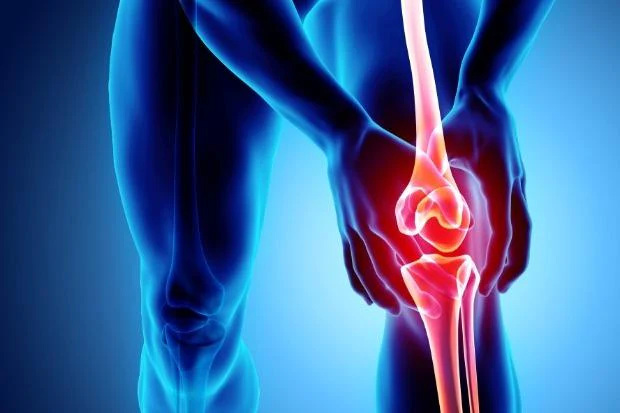

Nyeri sendi sering kali dianggap sebagai masalah ringan. Banyak orang mengira rasa nyeri di lutut, pinggang, atau tangan hanyalah akibat kelelahan atau faktor usia. Akibatnya, keluhan ini sering diabaikan dan tidak ditangani dengan serius.

Padahal, di balik gejala yang terlihat sederhana, bisa saja terdapat kondisi yang lebih kompleks, seperti osteoartritis—penyakit sendi yang berkembang secara perlahan namun dapat berdampak besar pada kualitas hidup.

Osteoartritis adalah kondisi di mana tulang rawan pada sendi mengalami kerusakan secara bertahap. Tulang rawan ini berfungsi sebagai bantalan yang melindungi ujung tulang agar tidak saling bergesekan.

Ketika bantalan ini menipis atau rusak:

gesekan antar tulang meningkat

muncul rasa nyeri

sendi menjadi kaku dan sulit digerakkan

lutut